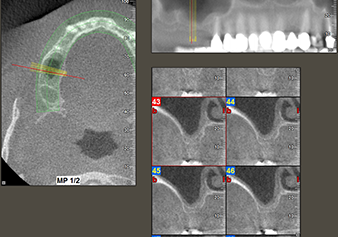

A 49-year-old female patient, a non-smoker and with nothing remarkable in her general medical history, was referred to our oral surgery practice for surgical extraction of tooth 16 and subsequent implantation. After the extraction, the patient experienced mild sinusitis trouble with the resultthat we initially waited six months before carrying out the measure. The residual bone height at the planned implant position measured 3-4 mm (Fig. 1 and 2).